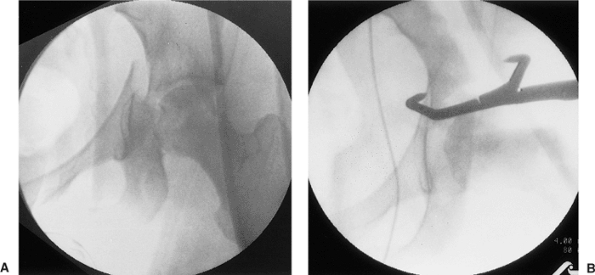

![]() |

Figure 41.6.

Selected two-dimensional CT sections through the dome of the acetabulum. In addition to findings consistent with a juxtatectal transverse and associated posterior-wall fracture, comminution involving the articular surface and quadrilateral plate is evident. |